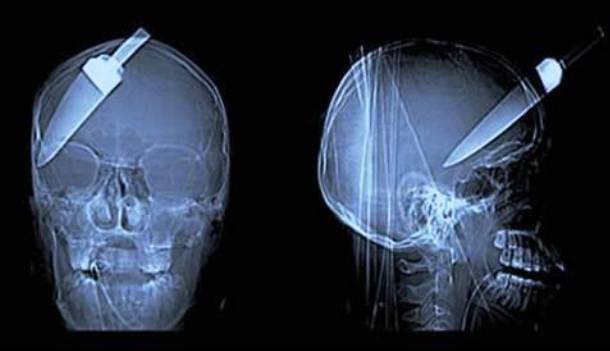

3. Chàng 'Lục Vân Tiên' xui xẻo

Khi một nhóm các chàng trai trẻ đang chờ xe bus quyết định tham gia vào ngăn chặn một vụ cướp vào năm 2008, một trong số các chàng trai này đã bị kháng cự và đâm.... ngập trán bằng một con dao. Ngạc nhiên hơn nữa là anh chàng này đã trải qua phẫu thuật thành công và hồi phục một cách đáng ngạc nhiên...

4. ...còn anh này thì không...

Đừng mất công tưởng tượng kỳ tích làm gì, anh chàng này thì chỉ đơn giản là đã chết cứng. Đây là phim chụp X-quang phục vụ công tác giám định tử thi, cho thấy anh này bị giết bằng một khẩu súng phóng đinh với hơn chục nhát bắn.